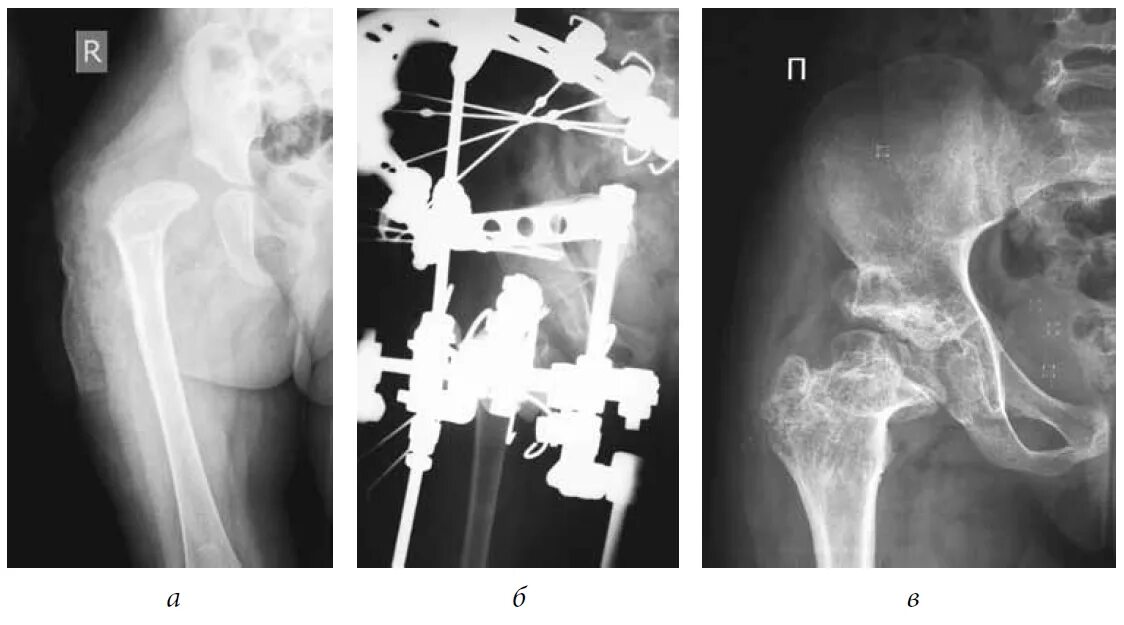

Упражнение тазобедренного сустава некроз